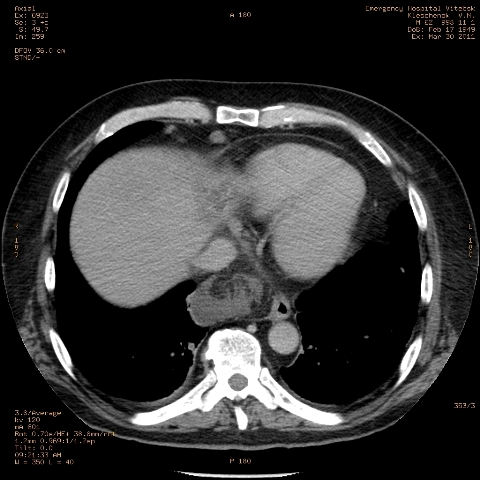

при исследовании органов брюшной полости по поводу абсцесса печени, в нижнем этаже средостения выявлено образование неоднородной плотности (-5-+25), при в/в контрастировании - не контрастируется, при per os - затёков из пищевода нет, неправильно овальной формы. предположительно киста перикарда? спасибо за помощь!

Может быть enteric duplication cyst. Как бы есть грыжа жира hiatal. И что с печенью? Мало срезов.